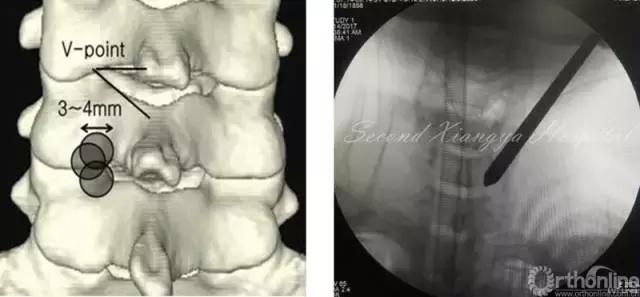

颈椎后路锁孔:颈椎后路结构单一,穿刺的靶点指向病变节段上椎板下缘、关节突和下椎板上缘组成的“V”点偏外骨性结构,穿刺端避免偏内落入椎管误伤脊髓。

同时,侧位透视时应调整C-Arm角度,也可通过C臂聚焦来显露被肩胛骨遮挡的下颈椎区域,从而帮助准确定位手术节段和防止穿刺后工作套管置入过深。

颈椎后路经椎间孔入路骨性标志点为“V”点,操作时注意“靶区触骨,动力先行,显根上下,脊髓勿碰。”也就是说,建立靶区应落到V点骨性结构部分,再用动力沿V点磨除外层皮质骨,黄韧带边缘会自然显露,再用Kerrison钳扩大显露神经根肩部与腋部,用神经勾进行探查和髓核摘除,手术全程都要注意保护脊髓,避免通过后方进行椎间隙髓核摘除这一危险操作。